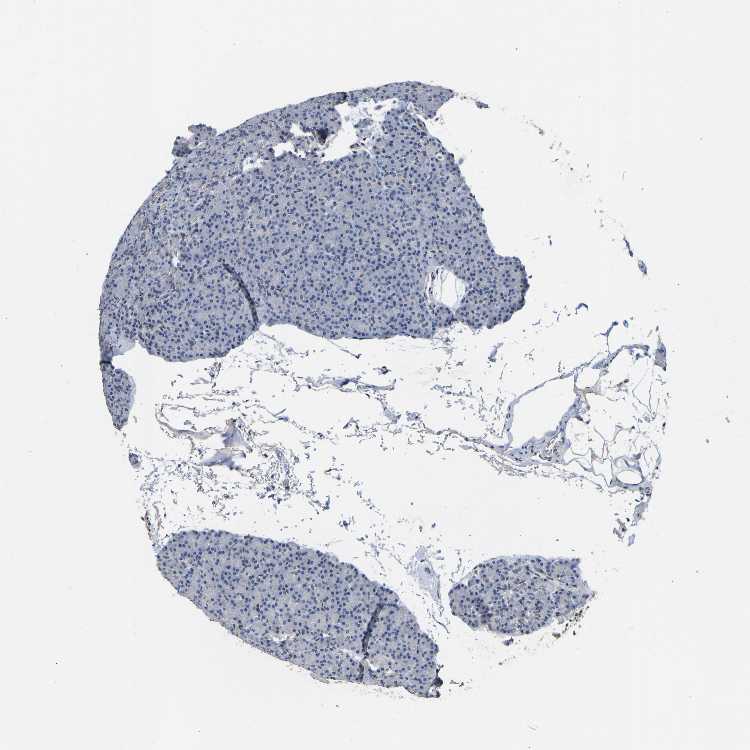

PANCREAS - Antibody stainingi

Antibody staining in the annotated cell types in the current human tissue is reported as not detected, low, medium, or high, based on conventional immunohistochemistry profiling in selected tissues. This score is based on the combination of the staining intensity and fraction of stained cells.

Each image is clickable and will lead to virtual microscopy that enables deeper exploration of all samples and also displays staining intensity scores, fraction scores and subcellular localization as well as patient and tissue information for each sample.

Antibody HPA019123Antibody CAB022602

Exocrine glandular cells Not detectedNot detected

Pancreatic endocrine cells Not detectedNot detected